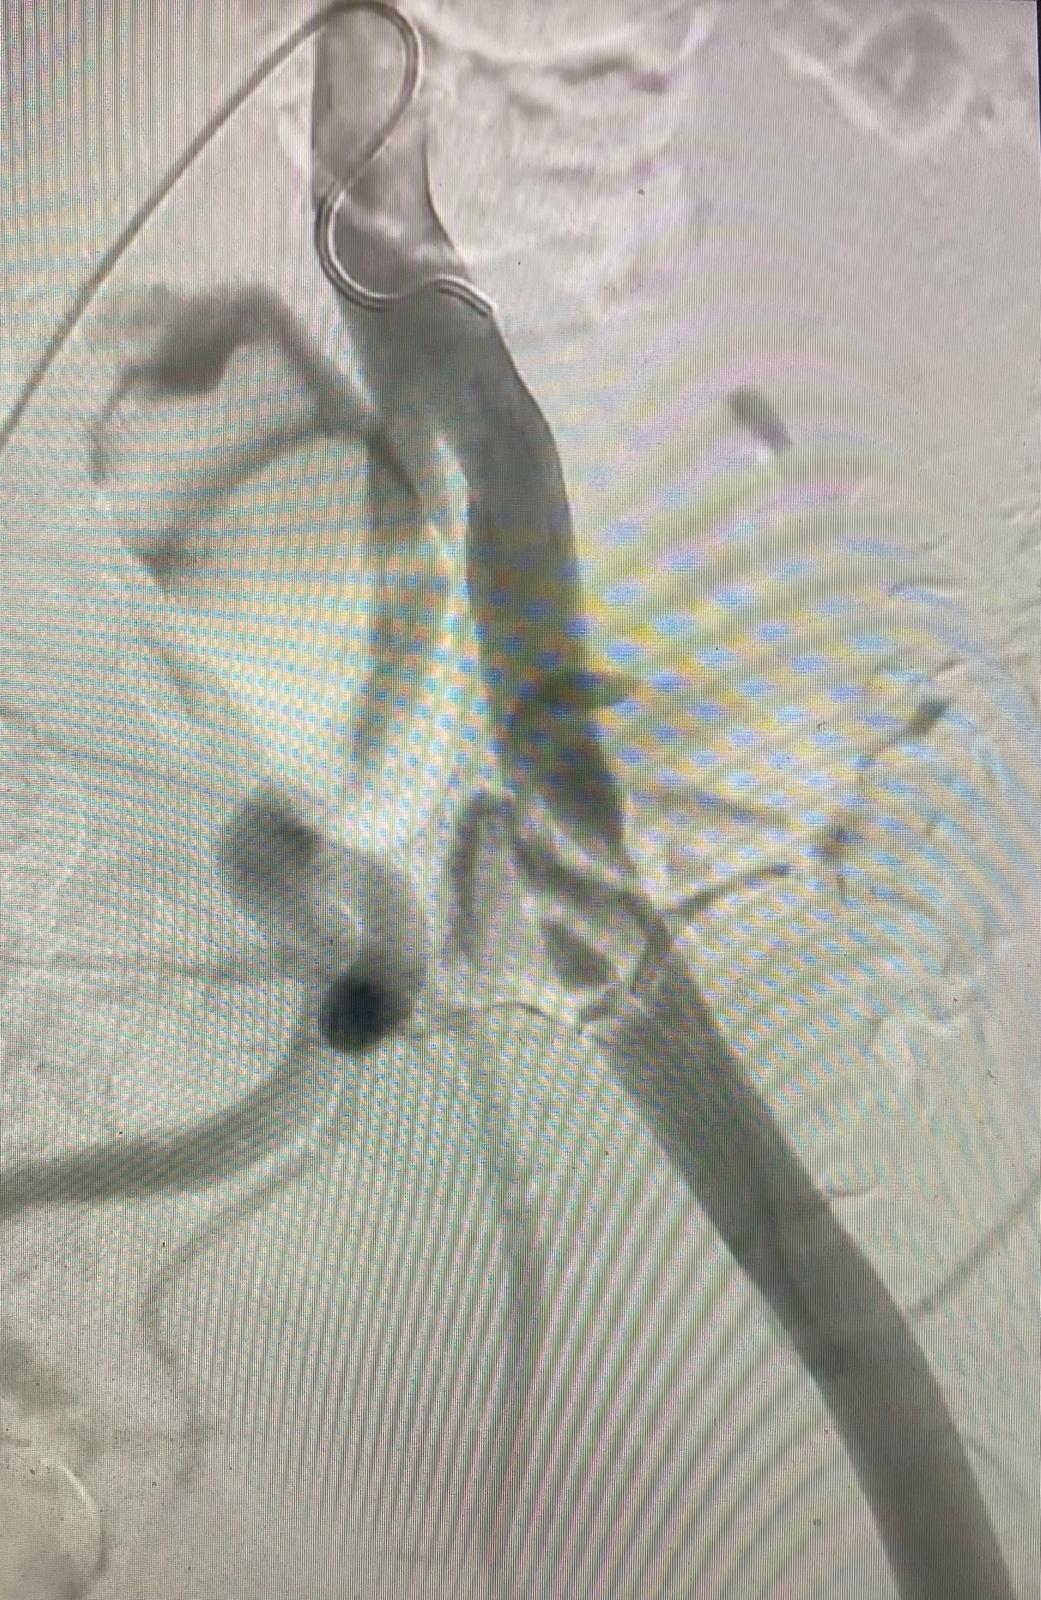

Recientemente he intervenido un nuevo caso de endofibrosis de la arteria ilíaca externa en un ciclista profesional, con afectación del sector ilíaco izquierdo. Se trata de una patología poco frecuente, característica de deportistas de resistencia, que se manifiesta mediante claudicación durante el ejercicio en ausencia de enfermedad aterosclerótica clásica.

El procedimiento se llevó a cabo en el Hospital Quirónsalud A Coruña, en un entorno de máxima especialización y con la colaboración del Dr. Ignacio Lojo, cuya experiencia y apoyo han sido fundamentales. Asimismo, quiero destacar la valiosa participación del Dr. Javier Barreiro y del Dr. Alejandro Moro, que contribuyeron al correcto desarrollo de la intervención.